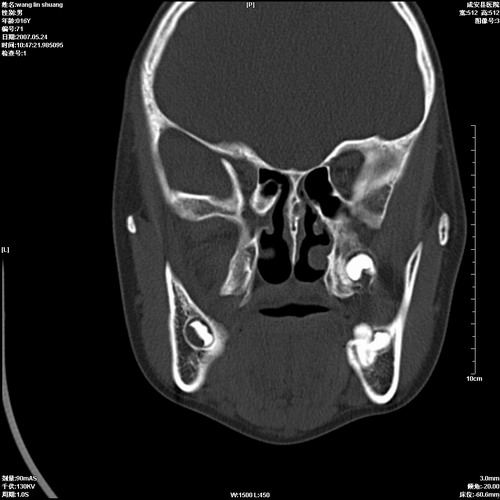

病人,男 16岁,鼻旁右肿胀,其余无不适感,ct图片

本人同意根尖囊肿,双侧上颌窦、筛窦、蝶窦炎.

1\\左侧根尖囊肿。

2、双侧上颌窦、筛窦、蝶窦炎

支持左侧根尖周囊肿,双侧上颌窦及左侧蝶窦炎。

1、左侧牙源性囊肿 2、双侧上颌窦炎.